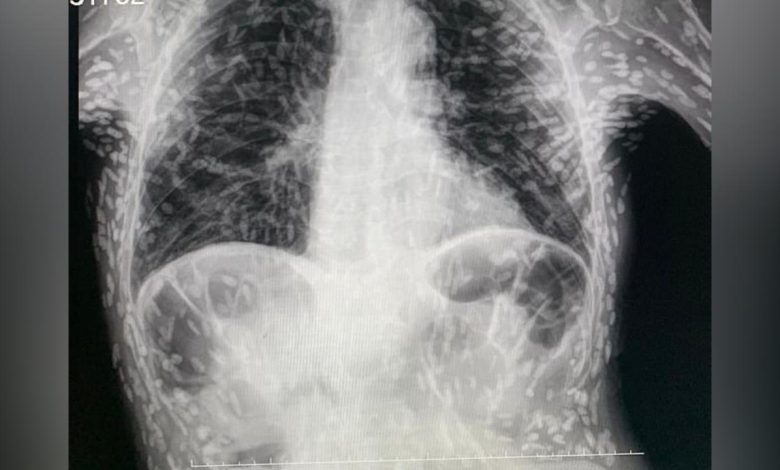

Hastanın röntgeninde yüzlerce beyaz nokta tespit edildi. Bu beyaz noktaların parazitlerin kireçlenmiş kalıntıları olduğu ortaya çıktı.